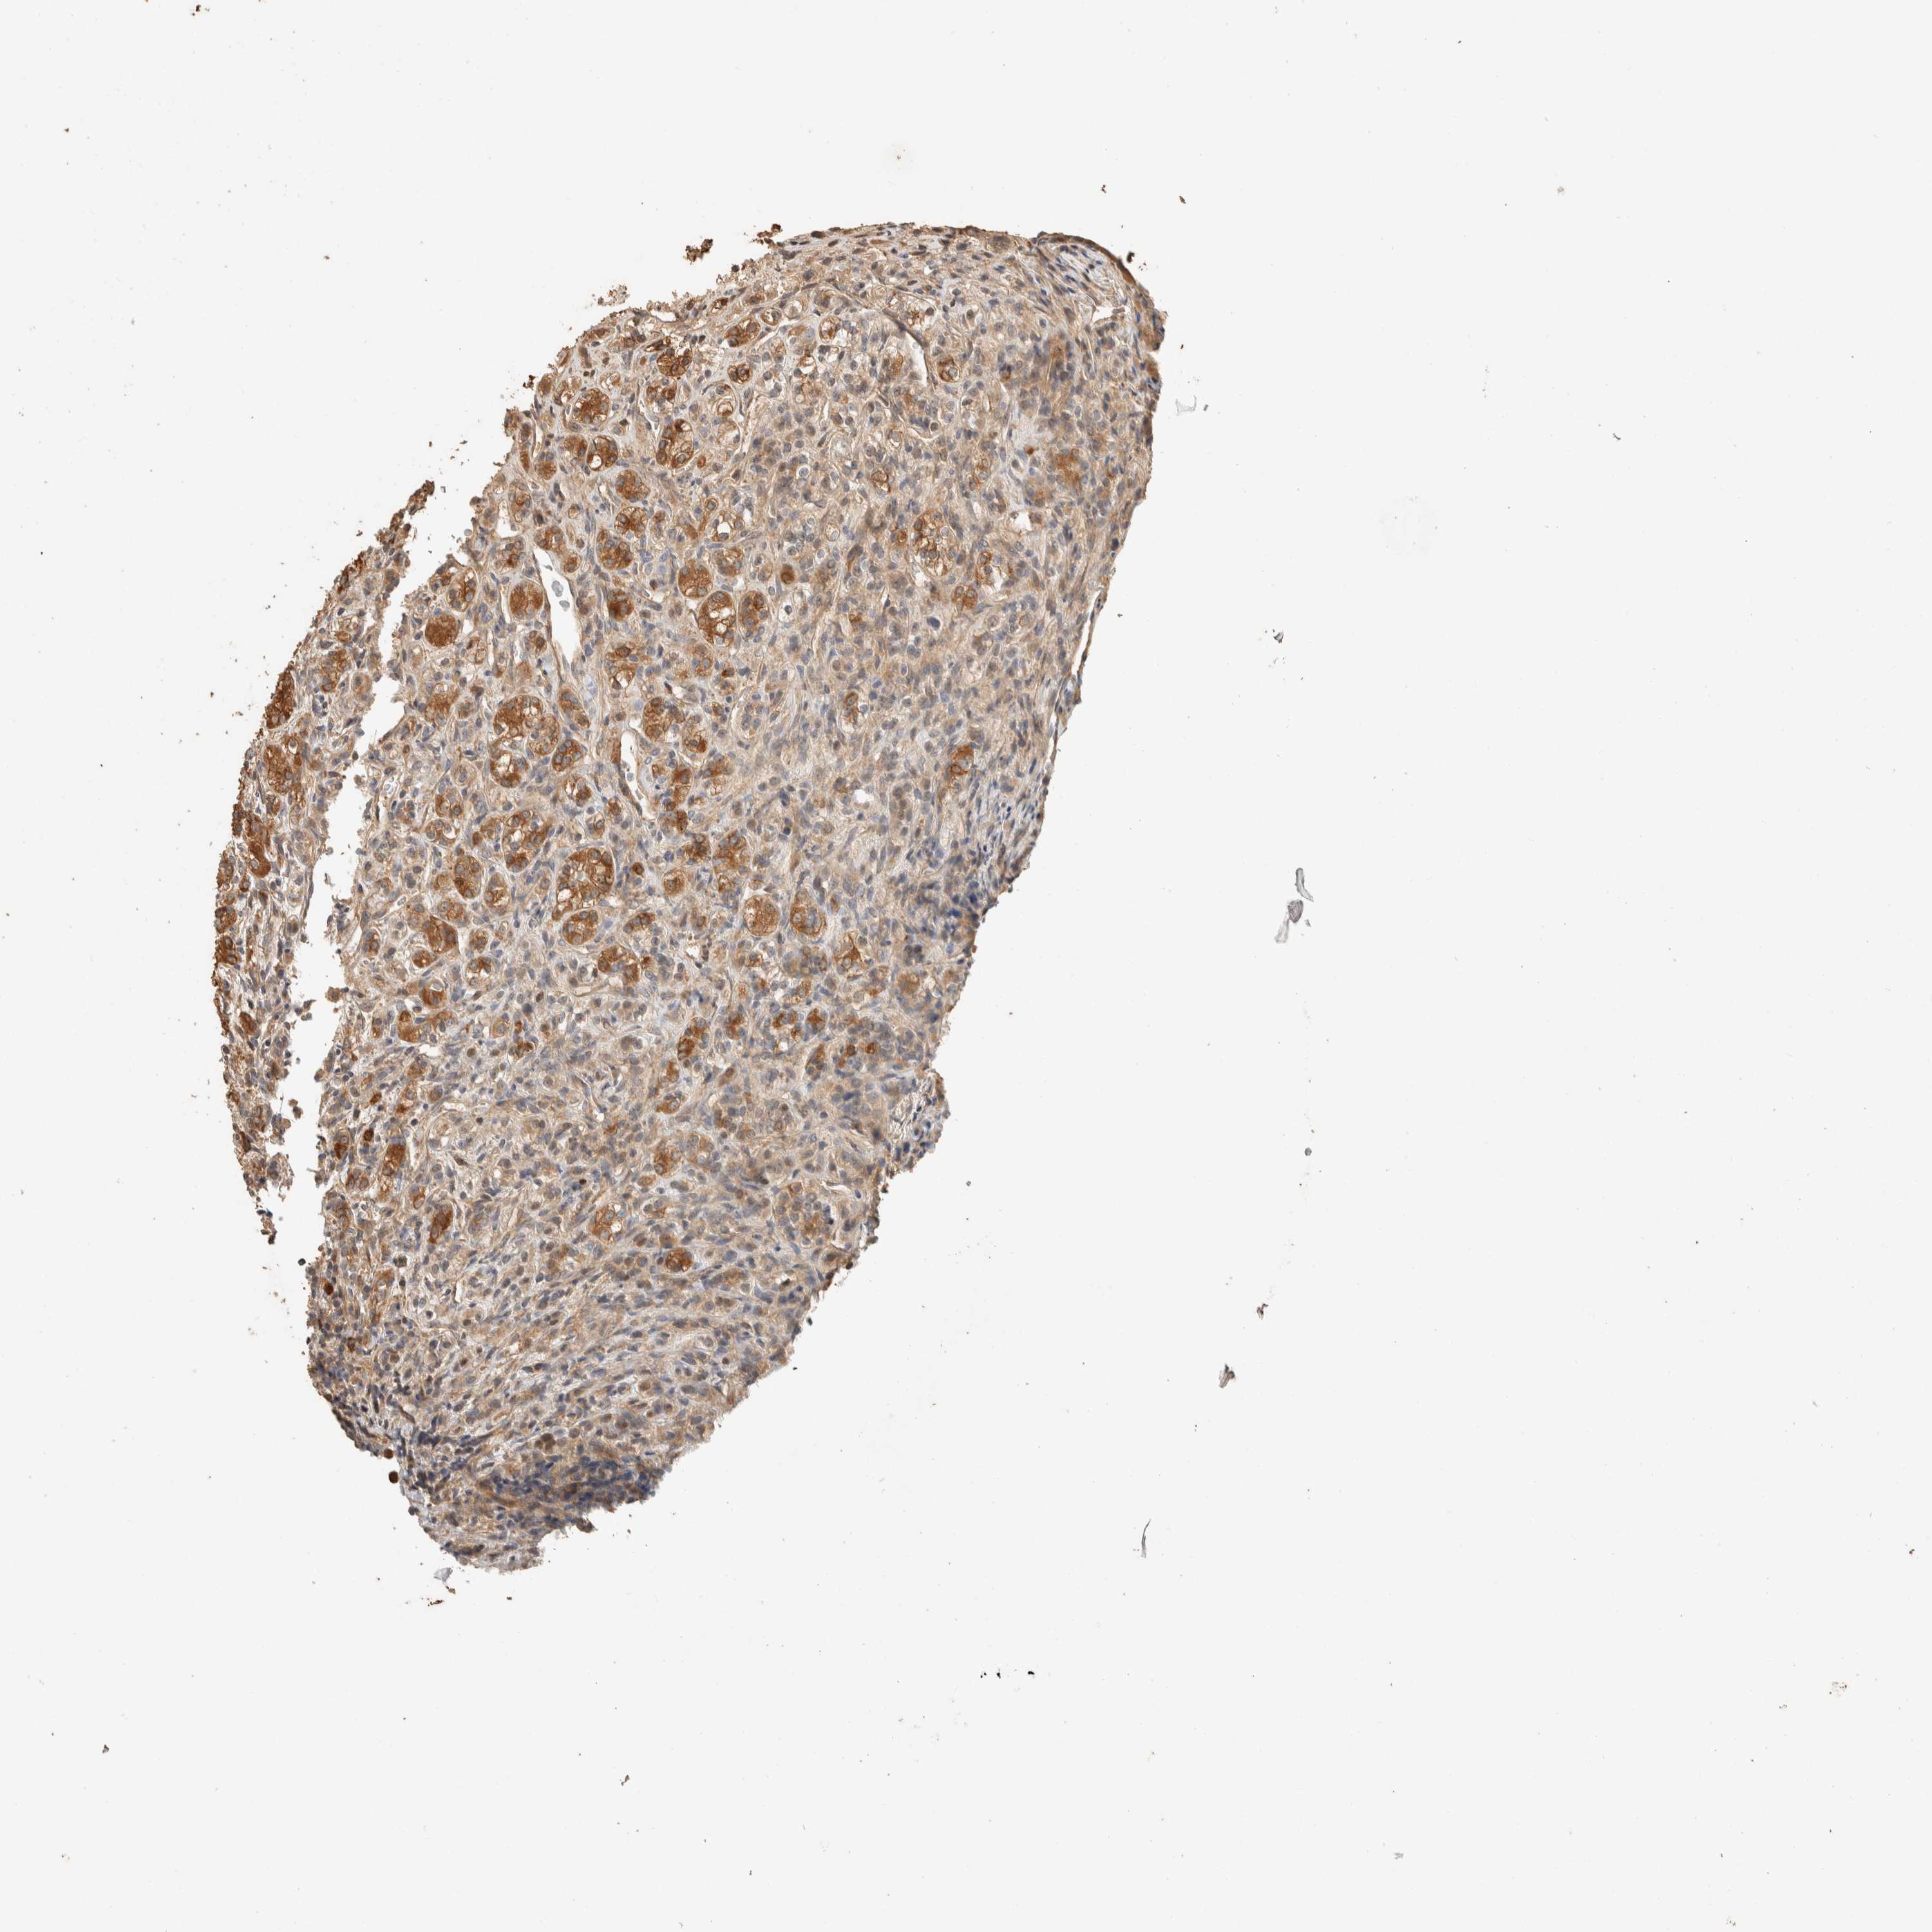

KIDNEY RENAL PAPILLARY CELL CARCINOMA (TCGA) - Interactive survival scatter ploti

The Survival Scatter plot shows the clinical status (i.e. dead or alive) for all individuals in the patient cohort, based on the same data that underlies the corresponding Kaplan-Meier plots. Patients that are alive at last time for follow-up are shown in blue and patients who have died during the study are shown in red.

The x-axis shows the expression levels (FPKM) of the investigated gene in the tumor tissue at the time of diagnosis. The y-axis shows the follow-up time after diagnosis (years). Both axes are complimented with kernel density curves demonstrating the data density over the axes. The top density plot shows the expression levels (FPKM) distribution among dead (red) and alive patients (blue). The right density plot shows the data density of the survived years of dead patients with high and low expression levels respectively, stratified using the cutoff indicated by the vertical dashed line through the Survival Scatter plot. This cutoff is automatically defined based on the FPKM cutoff that minimizes the p-score. The cutoff can be changed by dragging the vertical line or by entering a cutoff value in the square labeled "Current cut-off".

Under the Survival Scatter plot the p-score landscape (black curve; left axis) is shown together with dead median separation (red curve; right axis). Dead median separation is the difference in median mRNA expression between patients who have died with high and low expression, respectively. It is calculated as follows: median FPKM expression of dead patients with high expression - median FPKM expression of dead patients with low expression. This is intended to aid the user in visually exploring custom cutoffs and the associated p-scores and dead median separation.

Individual patient data is displayed and can be filtered by clicking on one or more of the category buttons on the top of the page. Categories describing expression level and patient information include: high, low, alive, dead, female, male and tumor stages. The scale of the x-axis can be toggled between linear and log-scale by clicking on the "x log" button. Mouse-over function shows TCGA ID, patient information and mRNA expression (FPKM) for each patient.

& Survival analysisi

Kaplan-Meier plots summarize results from analysis of correlation between mRNA expression level and patient survival. Patients were divided based on level of expression into one of the two groups "low" (under cut off) or "high" (over cut off). X-axis shows time for survival (years) and y-axis shows the probability of survival, where 1.0 corresponds to 100 percent.

EXOC7 is not prognostic in Kidney Renal Papillary Cell Carcinoma (TCGA)